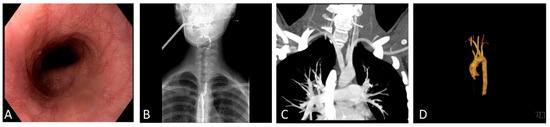

An Unusual Dysphagia for Solids in a 17-Year-Old Girl Due To a Lusoria Artery: A Case Report and Review of the Literature

2. Case Report